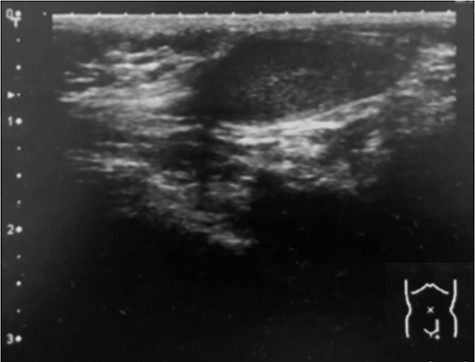

A14-month-old boy was admitted to our hospital to undergo inguinal orchidopexy. At the age of 1 month, the left testis was palpable between the inguinal canal and the scrotum. When he was 6 months old, ultrasonography showed the left testis inside the inguinal canal (Fig. 1). At the age of 13 months, the patient was seen in the outpatient clinic for preoperative examination in preparation for inguinal orchidopexy; the left testis was not palpable at that time. At the age of 14 months, we began surgery with a preoperative diagnosis of an undescended testis. When the inguinal canal was opened, only a patent processus vaginalis was visible (Fig. 2). After incision of the membrane, we were able to retrieve the testis from the abdominal cavity (Fig. 3a). The patent processus vaginalis was closed, a dartos pouch was created and the testis was guided into the pouch and fixed to its wall (Fig. 3b).

Ultrasonography (6 months of age). The left testis is located within the inguinal canal.